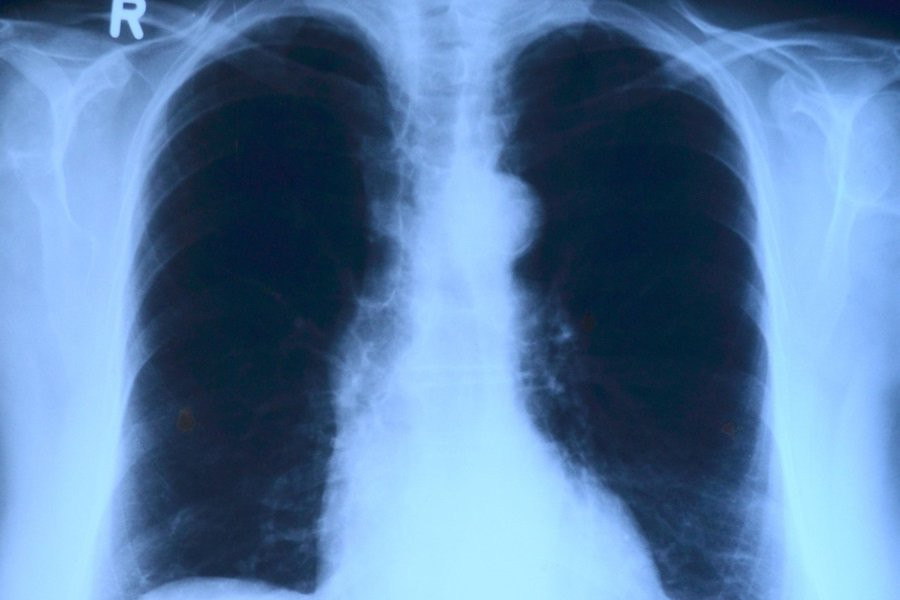

ИИ определяет возраст человека по рентгенограмме груди

Искусственный интеллект теперь способен определить возраст человека, анализируя рентгеновские снимки грудной клетки. Эту новость сообщает журнал The Lancet.

Исследователи из Высшей школы медицины Осаки (Япония) протестировали модель искусственного интеллекта на 67 099 рентгенограммах грудной клетки. Эти снимки были сделаны в период с 2008 по 2021 год и принадлежали 36 051 здоровому человеку. Модель искусственного интеллекта успешно определила связь между предполагаемым возрастом, вычисленным на основе анализа ИИ, и реальным хронологическим возрастом людей. Коэффициент корреляции составил 0,95, что свидетельствует об очень сильной связи между этими показателями. Дополнительно эксперты использовали 34 197 рентгенограмм грудной клетки от пациентов, у которых уже были диагностированы различные заболевания.

Исследование показало, что разница между возрастом, определенным искусственным интеллектом, и хронологическим возрастом пациента была связана с определенными заболеваниями. Вероятность наличия гипертонии, гиперурикемии и хронической обструктивной болезни легких увеличивалась с ростом предсказанного возраста, полученного ИИ.